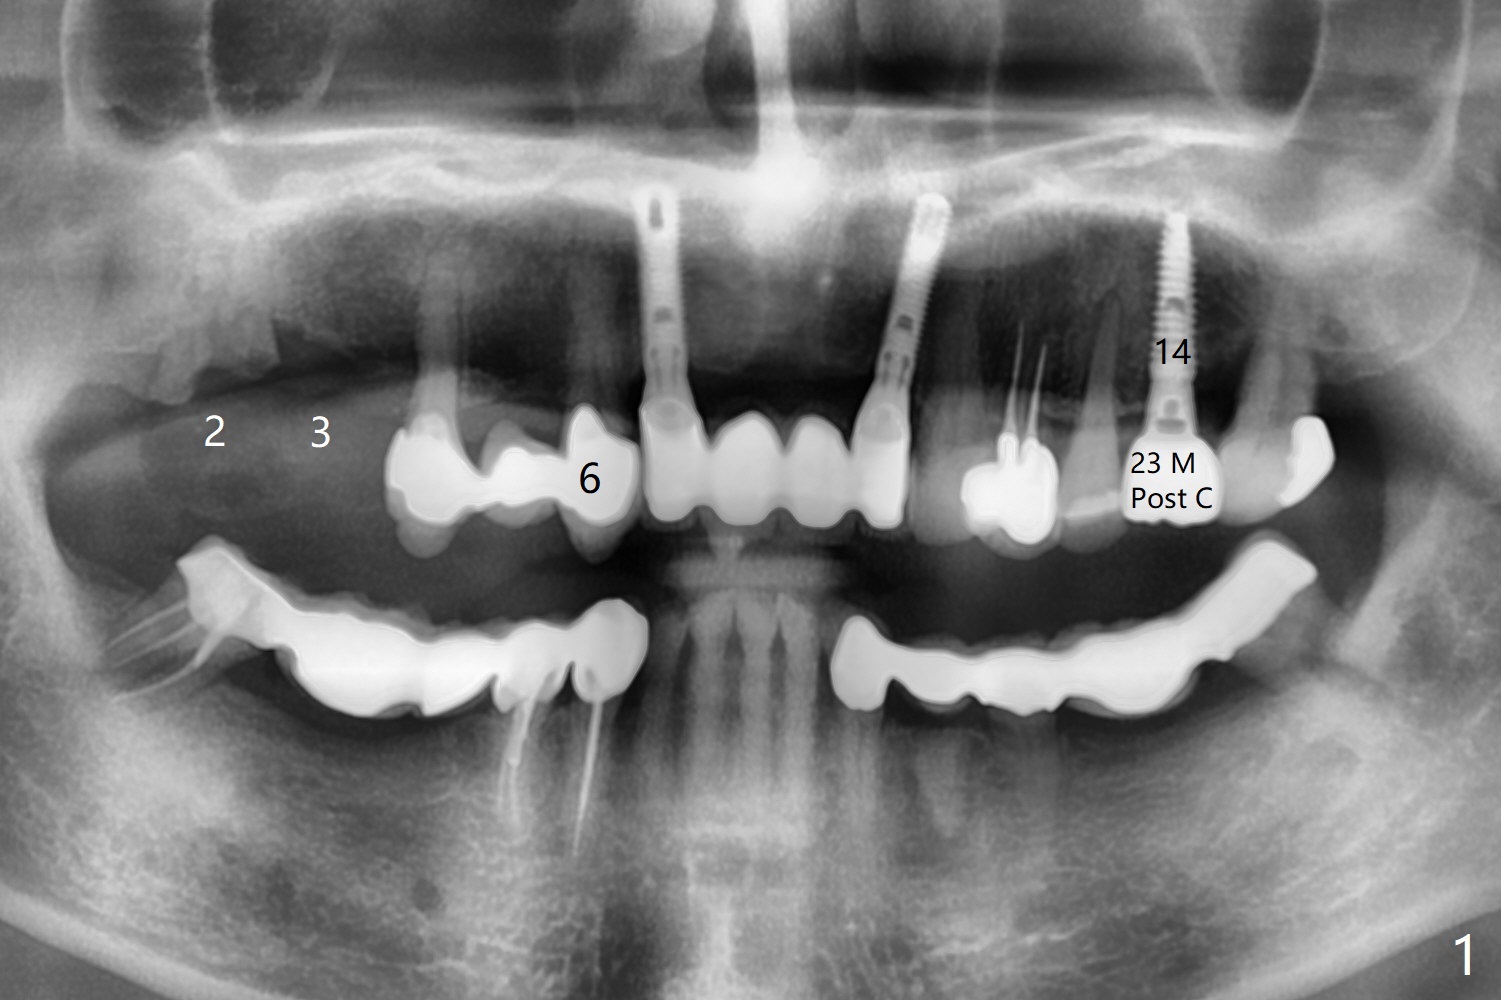

67岁男14号牙植牙牙冠粘固后两年回来处理右上(2-6)桥问题,撤除2,3单位(图一),准备种植(图二,三),3号牙牙槽嵴比较窄(图三),勉强植入4x10毫米植体,我想借助导板和它的钻头进行骨扩张,这样可以植入稍微大植体,例如4.5毫米。能不能最细钻头顺转,而再粗的钻头倒旋达到扩张目的?3号牙牙槽骨平均密度650单位。